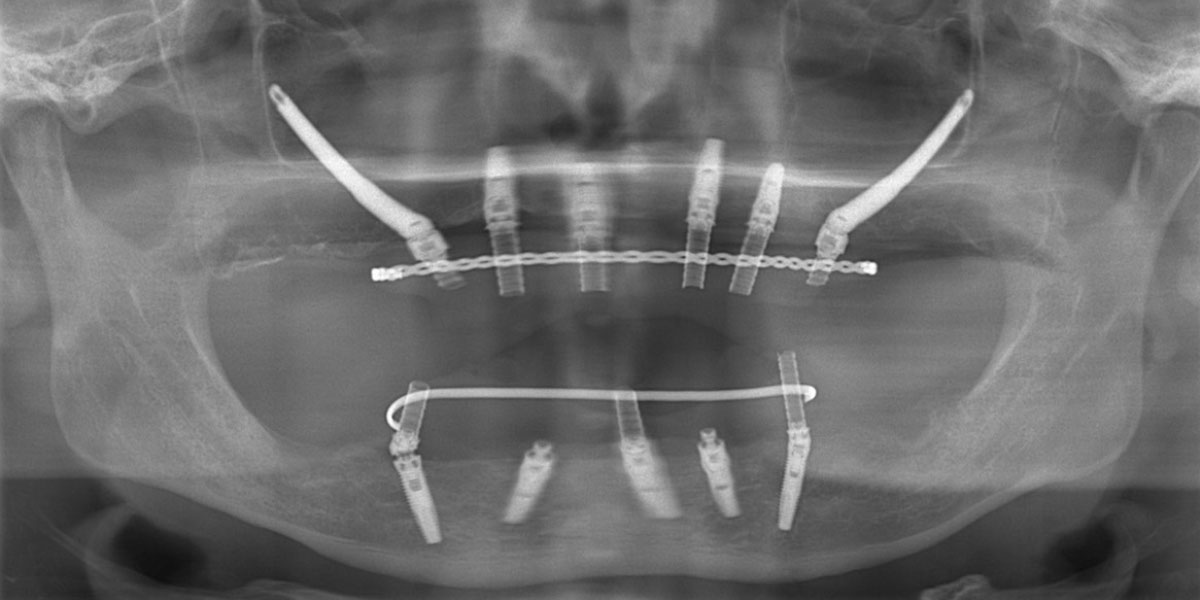

手術後パノラマX線写真

全体的に歯がボロボロで噛むと痛みがあると訴えあり。インプラント埋入可能な歯槽骨量が少なく、残存歯も抜歯対象のため上下ザイゴマインプラント治療を選択。